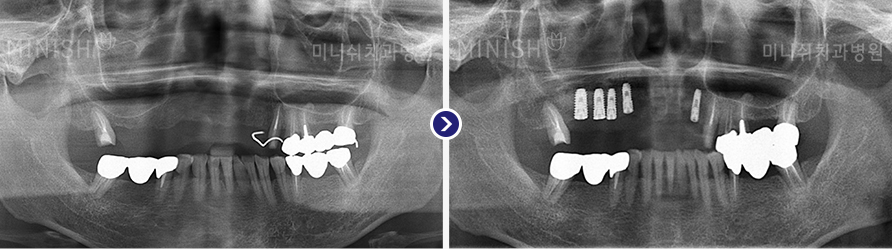

种植牙前后变化

01 X光片